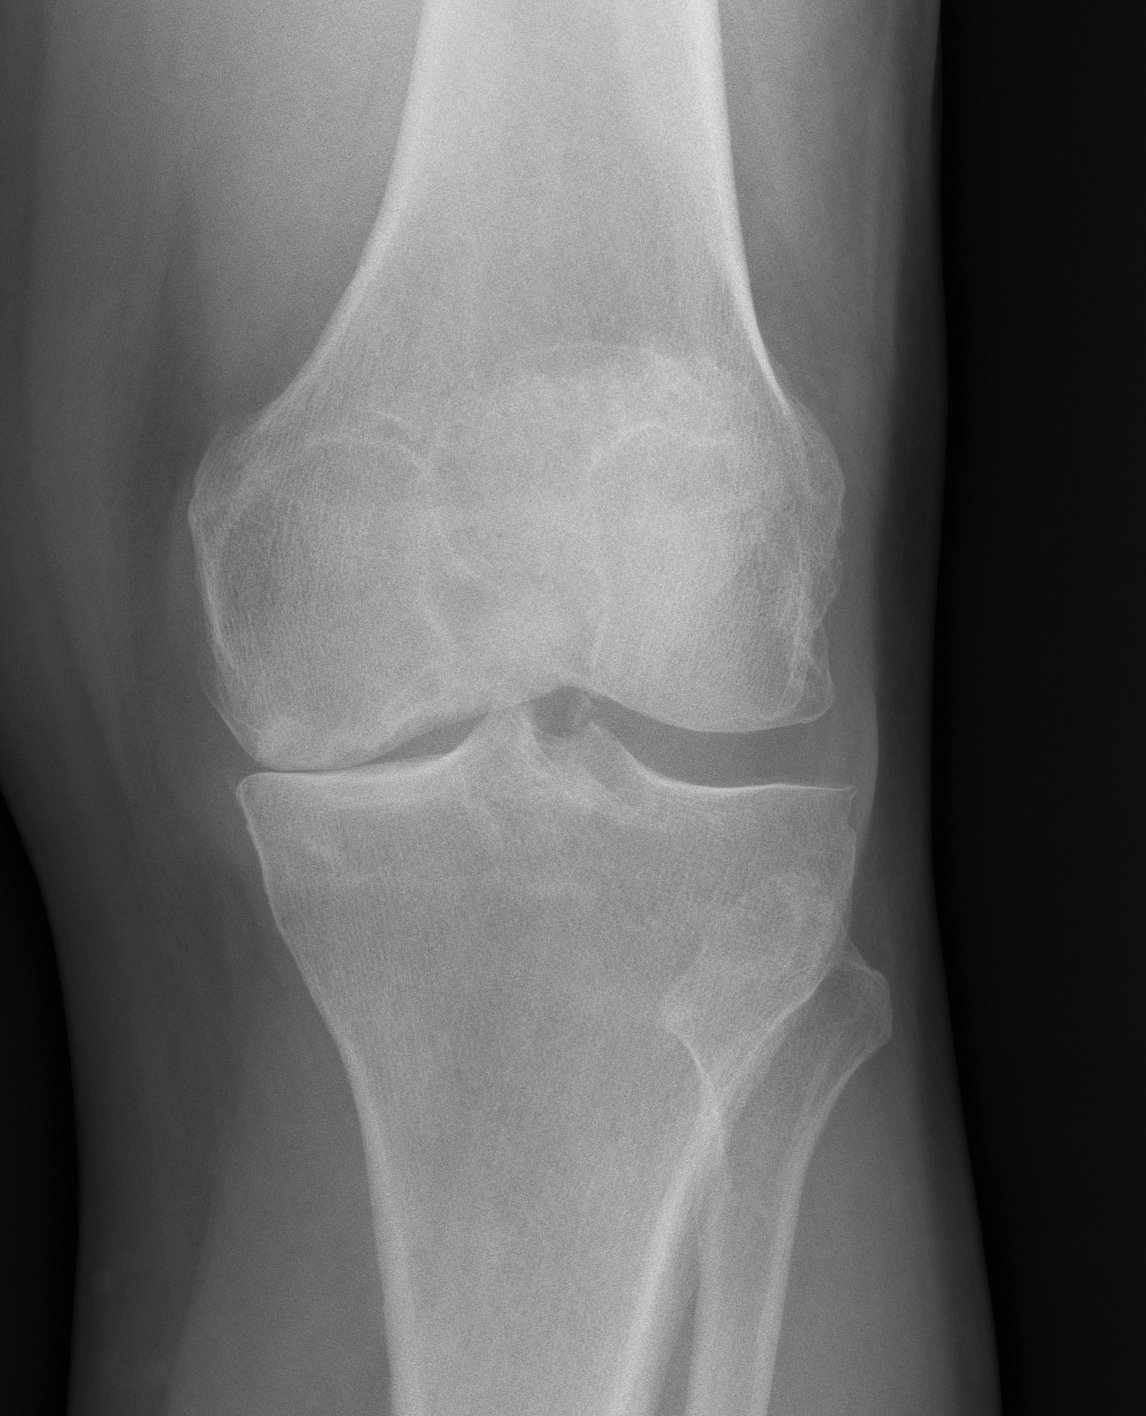

X-rays

AP / Lateral / Skyline

Patient 2